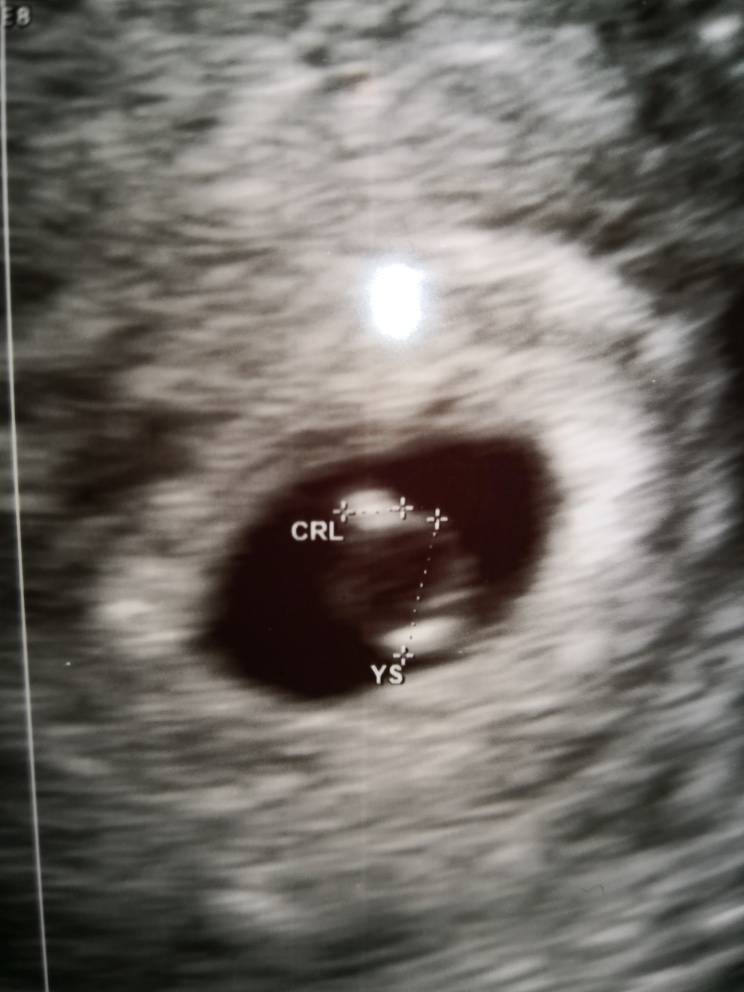

Nasze 1,5 mm Szczęścia [emoji7]Zobacz załącznik 926896

Gratulacje jeszcze raz :* dużo zdrówka :*Nasze 1,5 mm Szczęścia [emoji7]Zobacz załącznik 926896

Piękny Maluszek [emoji7]Nasze 1,5 mm Szczęścia [emoji7]Zobacz załącznik 926896